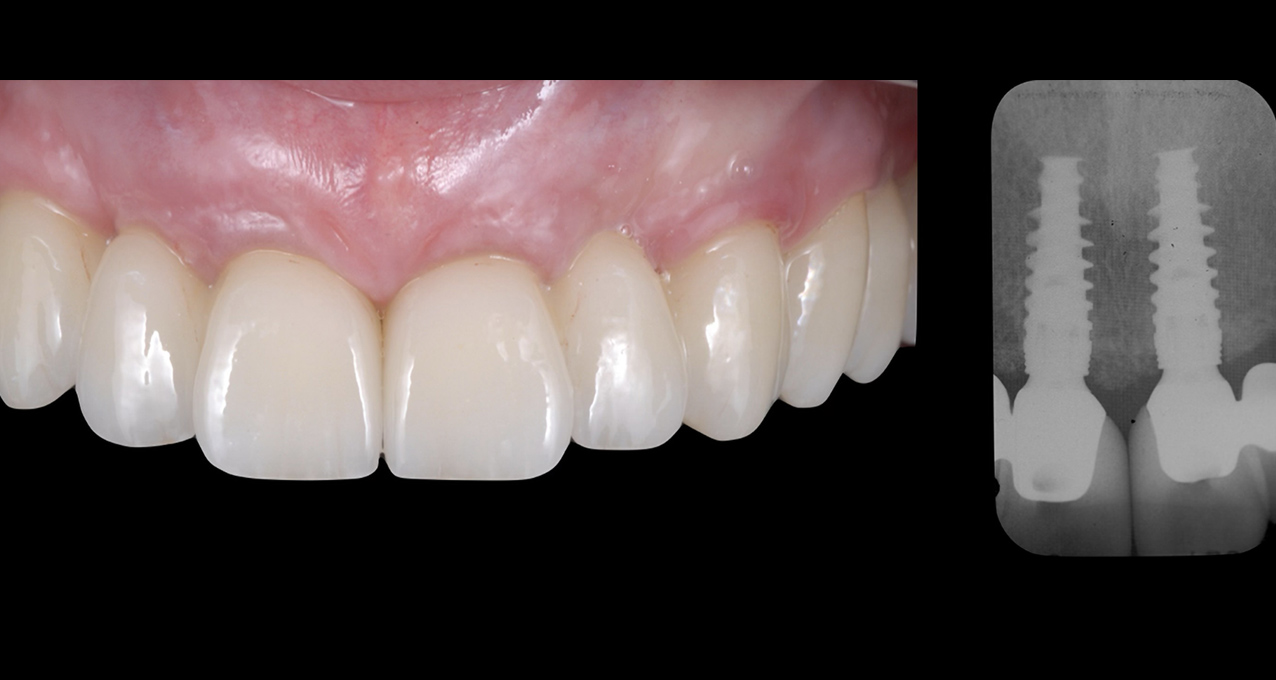

We recently completed a same-day digital full-arch implant treatment using in-office 3D printed stackable surgical guides and a 3D printed hybrid prosthesis. prosthesis. Advance your implant dentistry skills with the industry-leading Full Arch Implant Course for Dentists offered by gIDE Dental Institute. This comprehensive program is specifically designed for clinicians who want to master full-arch rehabilitation using predictable, evidence-based protocols. Whether you are new to full-arch procedures or looking to enhance your expertise, this course provides the clinical confidence and hands-on experience needed to succeed in modern implant dentistry.